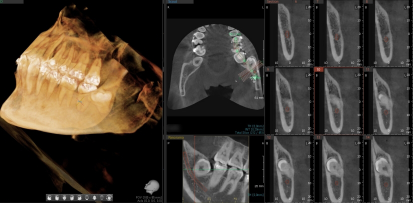

0.1mm 오차 없는 3D 매핑

단순 엑스레이로는 신경의 앞뒤 위치를 정확히 알 수 없습니다. 본원은 대학병원급 3D CT 정밀 진단을 통해 사랑니 뿌리와 하치조신경 사이의 거리를 3차원으로 입체 분석합니다. 신경 손상 위험을 사전에 시뮬레이션하여 감각 이상 부작용을 원천 차단하는 안전한 경로를 설계합니다.